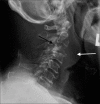

Lateral projection of cervical spine radiograph. Lytic cervical spine lesion at C3 level with partial vertebral collapse (black arrow). It was associated with prevertebral soft-tissue swelling spanning from C2 to C4 levels (white arrow).

(a) Plain CT cervical spine. Cervical spine tumor at C2–C3 levels. It was associated with prevertebral soft-tissue mass spanning across C2–C4 levels with intratumoral calcifications within (white arrow). There was epidural involvement at the anterior epidural space (black arrow). (b) Plain CT cervical spine. Bone destruction at C2 and C3 vertebrae. (c) Plain CT cervical spine. Involvement of the right C3 neuroforamen.

Contrast CT cervical spine. Encasement of the right vertebral artery which remained opacified (black arrow).